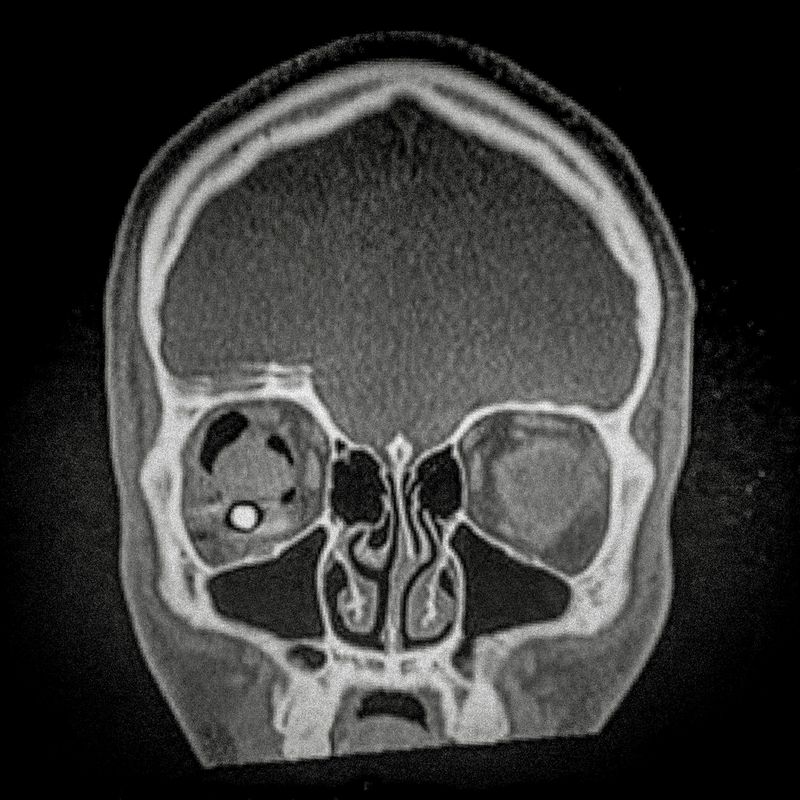

© Cristóbal Olivares - X ray showing the embedded pellet of Camilo Galvez (24) injured by chilean police during Santiago protests.

X ray showing the embedded pellet of Camilo Galvez (24) injured by chilean police during Santiago protests.

Camilo Galvez (24) Sound technician Lives in Puente Alto,Santiago Camilo was hit by a pellet that lodged into his right eye on November 15th, 2019, near the Universidad Católica de Chile in Santiago. His diagnosis was an eye burst with total loss of the right eye and fracture. “I lost an eye not because I had an accident, but because somebody shot me on purpose to mutilate me, and that is pretty hard. To think and reflect about this is very abysmal, it generates a lot of fear. When they shoot our eyes one becomes marked, it is their way of marking us, and leaves us with a psychological trauma beyond the physical mutilation.”